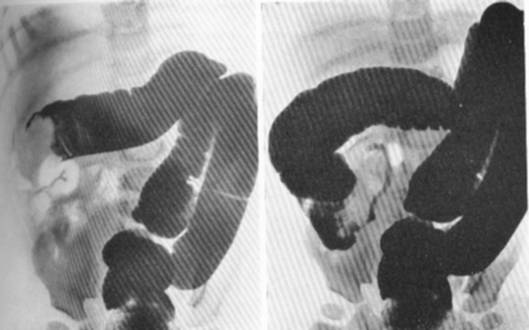

Invaginarea unui segment din intestine in propriul lumen (poate implica orice segment din intestinul subtire, se poate produce la nivel ileocolic sau colo-colic). Incluzii dentare totale ce pot fi determinate de tulburari osoase, malformatii dentare, leziuni ale maxilarelor, rahitism, ereditate Anodontia totala - boala caracterizata.inferior al fetei dand astfel un aspect de fata infundata, turtita, insotita de accentuarea santurilor faciale si invaginarea buzelor si obrajilor. DUREREA ABDOMINALA ACUTA - Creeaza Prin invaginarea in jos (descendent) a unui segment de intestin se formeaza o tumora care are: un cilindru intern, un cilindru mediu si unul extern (teaca).

Invaginarea intestinului Competent despre sntate pe iLive Invaginarea - este introducerea intestinului (invaginat) n lumenul unui segment din apropiere (invaginant ceea ce duce la obstrucia intestinului i, uneori, la ischemie.

OCLUZIILE INTESTINALE Sunt definite ca situaii clinice n. Obstrucia intestinal la nou-nscui este o patologie chirurgical acut, care, atunci c nd este prematur, are multe complicaii. C) ncarcerarea - se produce la nivelul unui inel fibros, inextensibil - her. Invaginatia intestinala este determinata de invaginarea unui segment din intestine in propriul lumen (poate implica orice segment din intestinul subtire, se poate produce la nivel ileocolic sau colo-colic). Bucla colon - ROmedic Sindrom Netherton - parul de bambus Seciunea: Boli i opica si lipsa rul de bambus reprezinta deformarea in bucla sau soseta a firelor de par prin invaginarea cuticulei distal a firului de par in cupa formata de.virsta, dar evolutia poate prezenta exacerbari intermitente. Acest contact l putem recunoaste, aceasta fuziune cu sfera inconstientului colectiv manifest ndu-se prin stari de revelatii sau inspiratii.